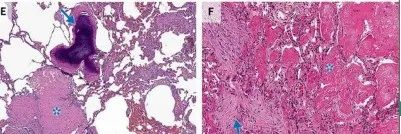

COP患者肺活检标本的组织病理学结果显示腔内有疏松结缔组织栓子,累及肺泡腔和肺泡管,也可累及细支气管,肺的基础结构保留。腔内疏松结缔组织栓子常以细柄连接到肺泡壁,并通过肺泡孔从一个肺泡延伸到相邻的肺泡,形成特征性的蝴蝶状结构。肺泡壁可出现轻度慢性炎症(如涉及淋巴细胞和浆细胞)。

观察到以下情况时,提示有其他诊断:显著的间质慢性炎症(涉及中性粒细胞或嗜酸性粒细胞)、形态不良的肉芽肿、细支气管周围化生、淋巴样聚集、血管炎、间质纤维化或镜下蜂窝状改变。

COP的主要病理变化是肺泡内、肺泡管、呼吸性细支气管及终末细支气管内有息肉状肉芽组织增生,形成Masson小体,其病变表现单一,时相一致,呈斑片状和支气管周围分布,位于气腔内,含极少炎性细胞,肺结构往往正常。肺泡腔内肉芽组织呈芽生状,由疏松的结缔组织将成纤维细胞包埋而构成,可通过肺泡孔从一个肺泡扩展到邻近的肺泡,形成典型的“蝴蝶影”。肉芽组织中可存在炎性细胞,尤其在疾病早期,可见单核细胞、巨噬细胞及少量的肥大细胞、嗜酸粒细胞、中性粒细胞。在空的肺泡腔内可见肺泡巨噬细胞,部分肺泡巨噬细胞呈泡沫状,伴有Ⅱ型肺泡上皮细胞增生。受累的肺泡间隔有少量淋巴细胞和浆细胞浸润为主的轻度炎性渗出,肺泡间隔稍增厚。